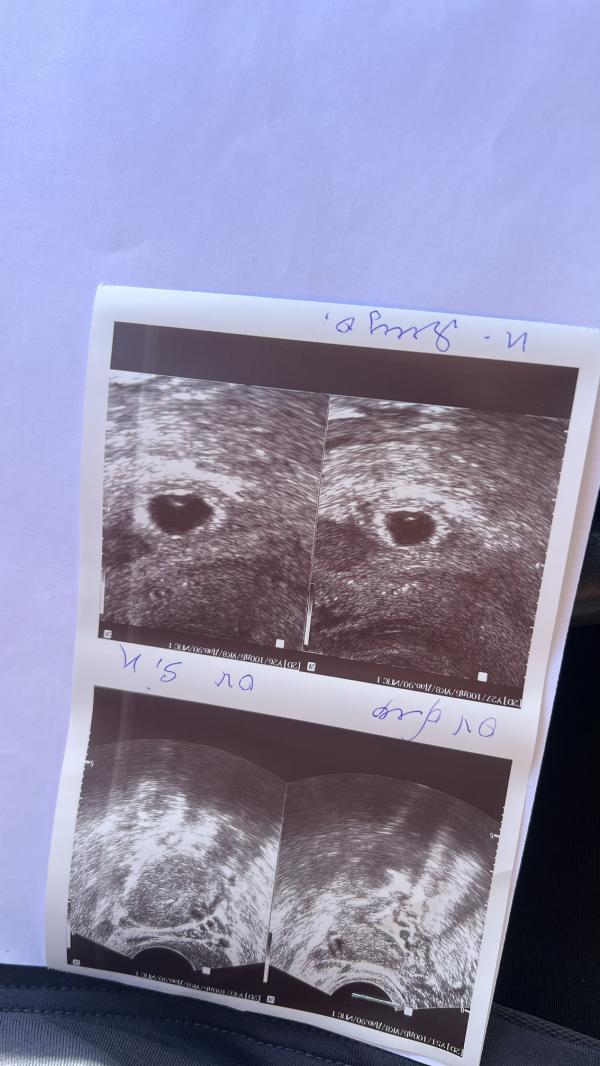

Сделала вчера первое узи на сроке 5,1 неделя -врач сказала ,что либо двойня либо что то не то ,переделала сегодня в другой клинике и сегодня уже пишут ,что есть плодовое яйцо и гемотома ,но на фото не видно ,так как навела в этот момент Не так ,пока водила там одинаковые два пятна ,одно круглое черное(то что на фото ),а другое вытянутое овальное практически такого же размера ….